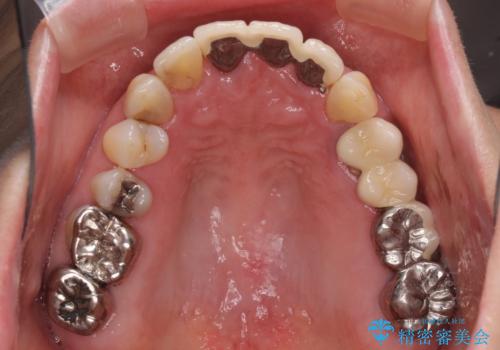

ブリッジの土台が割れて痛い インプラントによる補綴治療

- 上の奥歯に装着されているブリッジが痛むとのことで来院された患者様です。

診察した結果、ブリッジの土台となっている歯が割れていたため、抜歯が必要となりました。

欠損している歯数が多いため、ブリッジによる補綴治療は困難と判断し、インプラントによる補綴治療を行うこととしました。

インプラントを埋入するために必要な骨の高さがなかったため、上顎洞底の粘膜を挙上しました。

手術後は処置部に痣や腫脹が出現したり、痛みが出たりしましたが、補綴治療後は咬み合わせが安定し、大変満足していただきました。